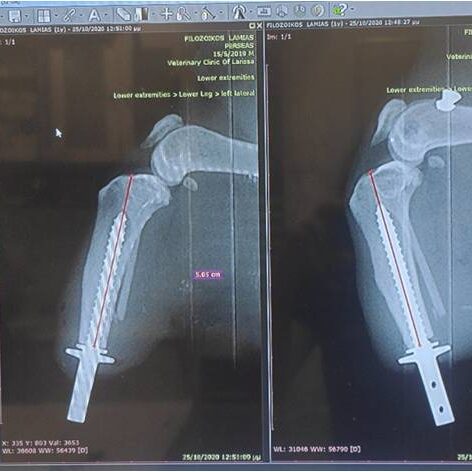

Η διαδικασία ξεκινά με μία αξονική τομογραφία στο Ιατρικό μας κέντρο στην Λευκάδα ή σε κάποιο συνεργαζόμενο με τον κτηνίατρο σας ιατρικό κέντρο. Μέσω αυτής λαμβάνουμε τα απαραίτητα CΤ-images όπου γίνεται ανάλυση  ψηφιακών δεδομένων με χρήση εξειδικευμένου ιατρικού λογισμικού Osirix-FDA.

Το επόμενο στάδιο είναι αυτό της προ-εγχειρητικής μελέτης-διάγνωσης, με σύγχρονες μεθόδους και εξοπλισμό όπως:

Με χρήση εξειδικευμένου μηχανολογικού λογισμικού CAD/CAM/CAE αναπτύσσουμε σε 3D ψηφιακή μορφή:

• την ανατομική περιοχή του οστού σε μορφή 3D όπου θα εφαρμοστεί το εμφύτευμα.

• το εξατομικευμένο εμφύτευμα τύπου ΙΤΑΡ.

Στη συνέχεια, γίνεται πιλοτική προσομοίωση προ-εγχειρητικά της εφαρμογής του οστού/εμφυτεύματος/έξω-προσθετικού με τα ακριβή ανατομικά πρωτότυπα μοντέλα, εξερευνώντας τα διαφορετικά στάδια υλοποίησης της και μελετώντας όλα τα πιθανά σενάρια.  Η κατασκευή του εξατομικευμένου εμφυτεύματος τύπου ITAP γίνεται με χρήση υπερσύγχρονου μηχανήματος κοπής CNC.